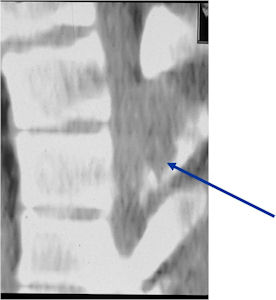

- Spine (40% of cases; usually posterior elements)

CT Scan:

- More useful for detecting mineralization and evaluating extent of bone destruction than plain X-ray

- Also useful in determining extent

- There is often extensive edema around the tumor in the surrounding bone and soft tissues that can lead to a misdiagnosis of a malignant tumor.